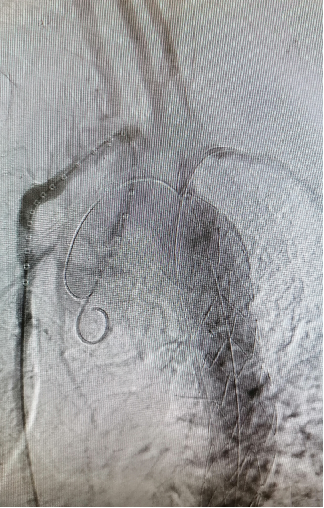

★Case 4 主动脉夹层+ARSA

治疗难点:弓上分支变异,迷走右锁骨下动脉+Kommerell憩室,夹层破口位于ARSA根部,累及LSA

手术策略:单分支支架,分支重建迷走右锁骨下动脉+续接覆膜支架

结果:假腔完全隔绝,弓上分支通畅